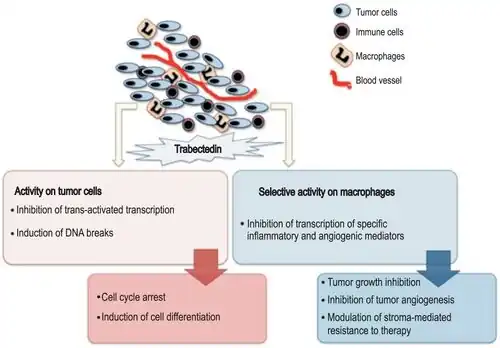

Mechanism of action

Recently, it has been shown that trabectedin blocks DNA binding of the oncogenic transcription factor FUS-CHOP and reverses the transcriptional program in myxoid liposarcoma. By reversing the genetic program created by this transcription factor, trabectedin promotes differentiation and reverses the oncogenic phenotype in these cells.[16]

Other than transcriptional interference, the mechanism of action of trabectedin is complex and not completely understood. The compound is known to bind and alkylate DNA at the N2 position of guanine. It is known from in vitro work that this binding occurs in the minor groove, spans approximately three to five bpbase pairs and is most efficient with CGG sequences. Additional favorable binding sequences are TGG, AGC, or GGC. Once bound, this reversible covalent adduct bends DNA toward the major groove, interferes directly with activated transcription, poisons the transcription-coupled nucleotide excision repair complex, promotes degradation of RNA polymerase II, and generates DNA double-strand breaks.[16]